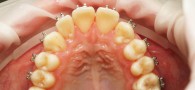

Установленная брекет-система не повод пропускать профгигиену! Наша пациентка обратилась к доктору Горяйновой Татьяне Сергеевне с вопросом, можно ли делать профессиональную чистку, если есть брекеты? Конечно, можно! И даже нужно каждые 3 месяца. Ответ удивил и обрадовал девушку, ведь здоровье зубов напрямую зависит от состояния полости рта.

Девушка полностью довольна итогом работы, эстетической и практической пользой для зубов и дёсен

После процедур Татьяна Сергеевна дала рекомендации по подбору индивидуальных средств ухода, которые замедляют повышенное налётообразование.

Были проведены следующие работы:

• Применение современной анестезии

• Снятие зубных отложений ультразвуковым методом

• Очистка эмали с помощью «Air Flow»

• Тщательная полировка зубов профессиональной пастой

• Обработка зубов для снижения чувствительности